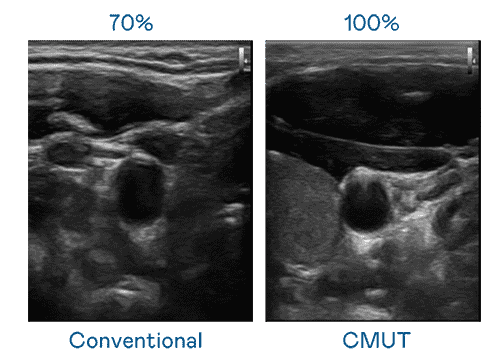

CMUT 技术是一种用电容式微机电元件来产生超音波讯号的技术。。。与传统 PZT 压电式技术相比,,,,CMUT 频宽增加 30%,,,,更宽频的超音波讯号让影像解析度大幅提升,,,,是实现高影像品质医疗超音波扫描、、、、促进精准医疗发展的关键技术。。。

大频宽带来超清晰影像

超音波影像的解析度高低,,首先取决于探头能发出的讯号频宽。。。云顶国际8588yd CMUT 可提供高清晰的超音波讯号,,,,提供高频宽、、、高灵敏度、、、影像纹理细节更高的超音波影像,,协助医护人员缩短影像判读时间及利用精准的医疗影像进行诊断。。。